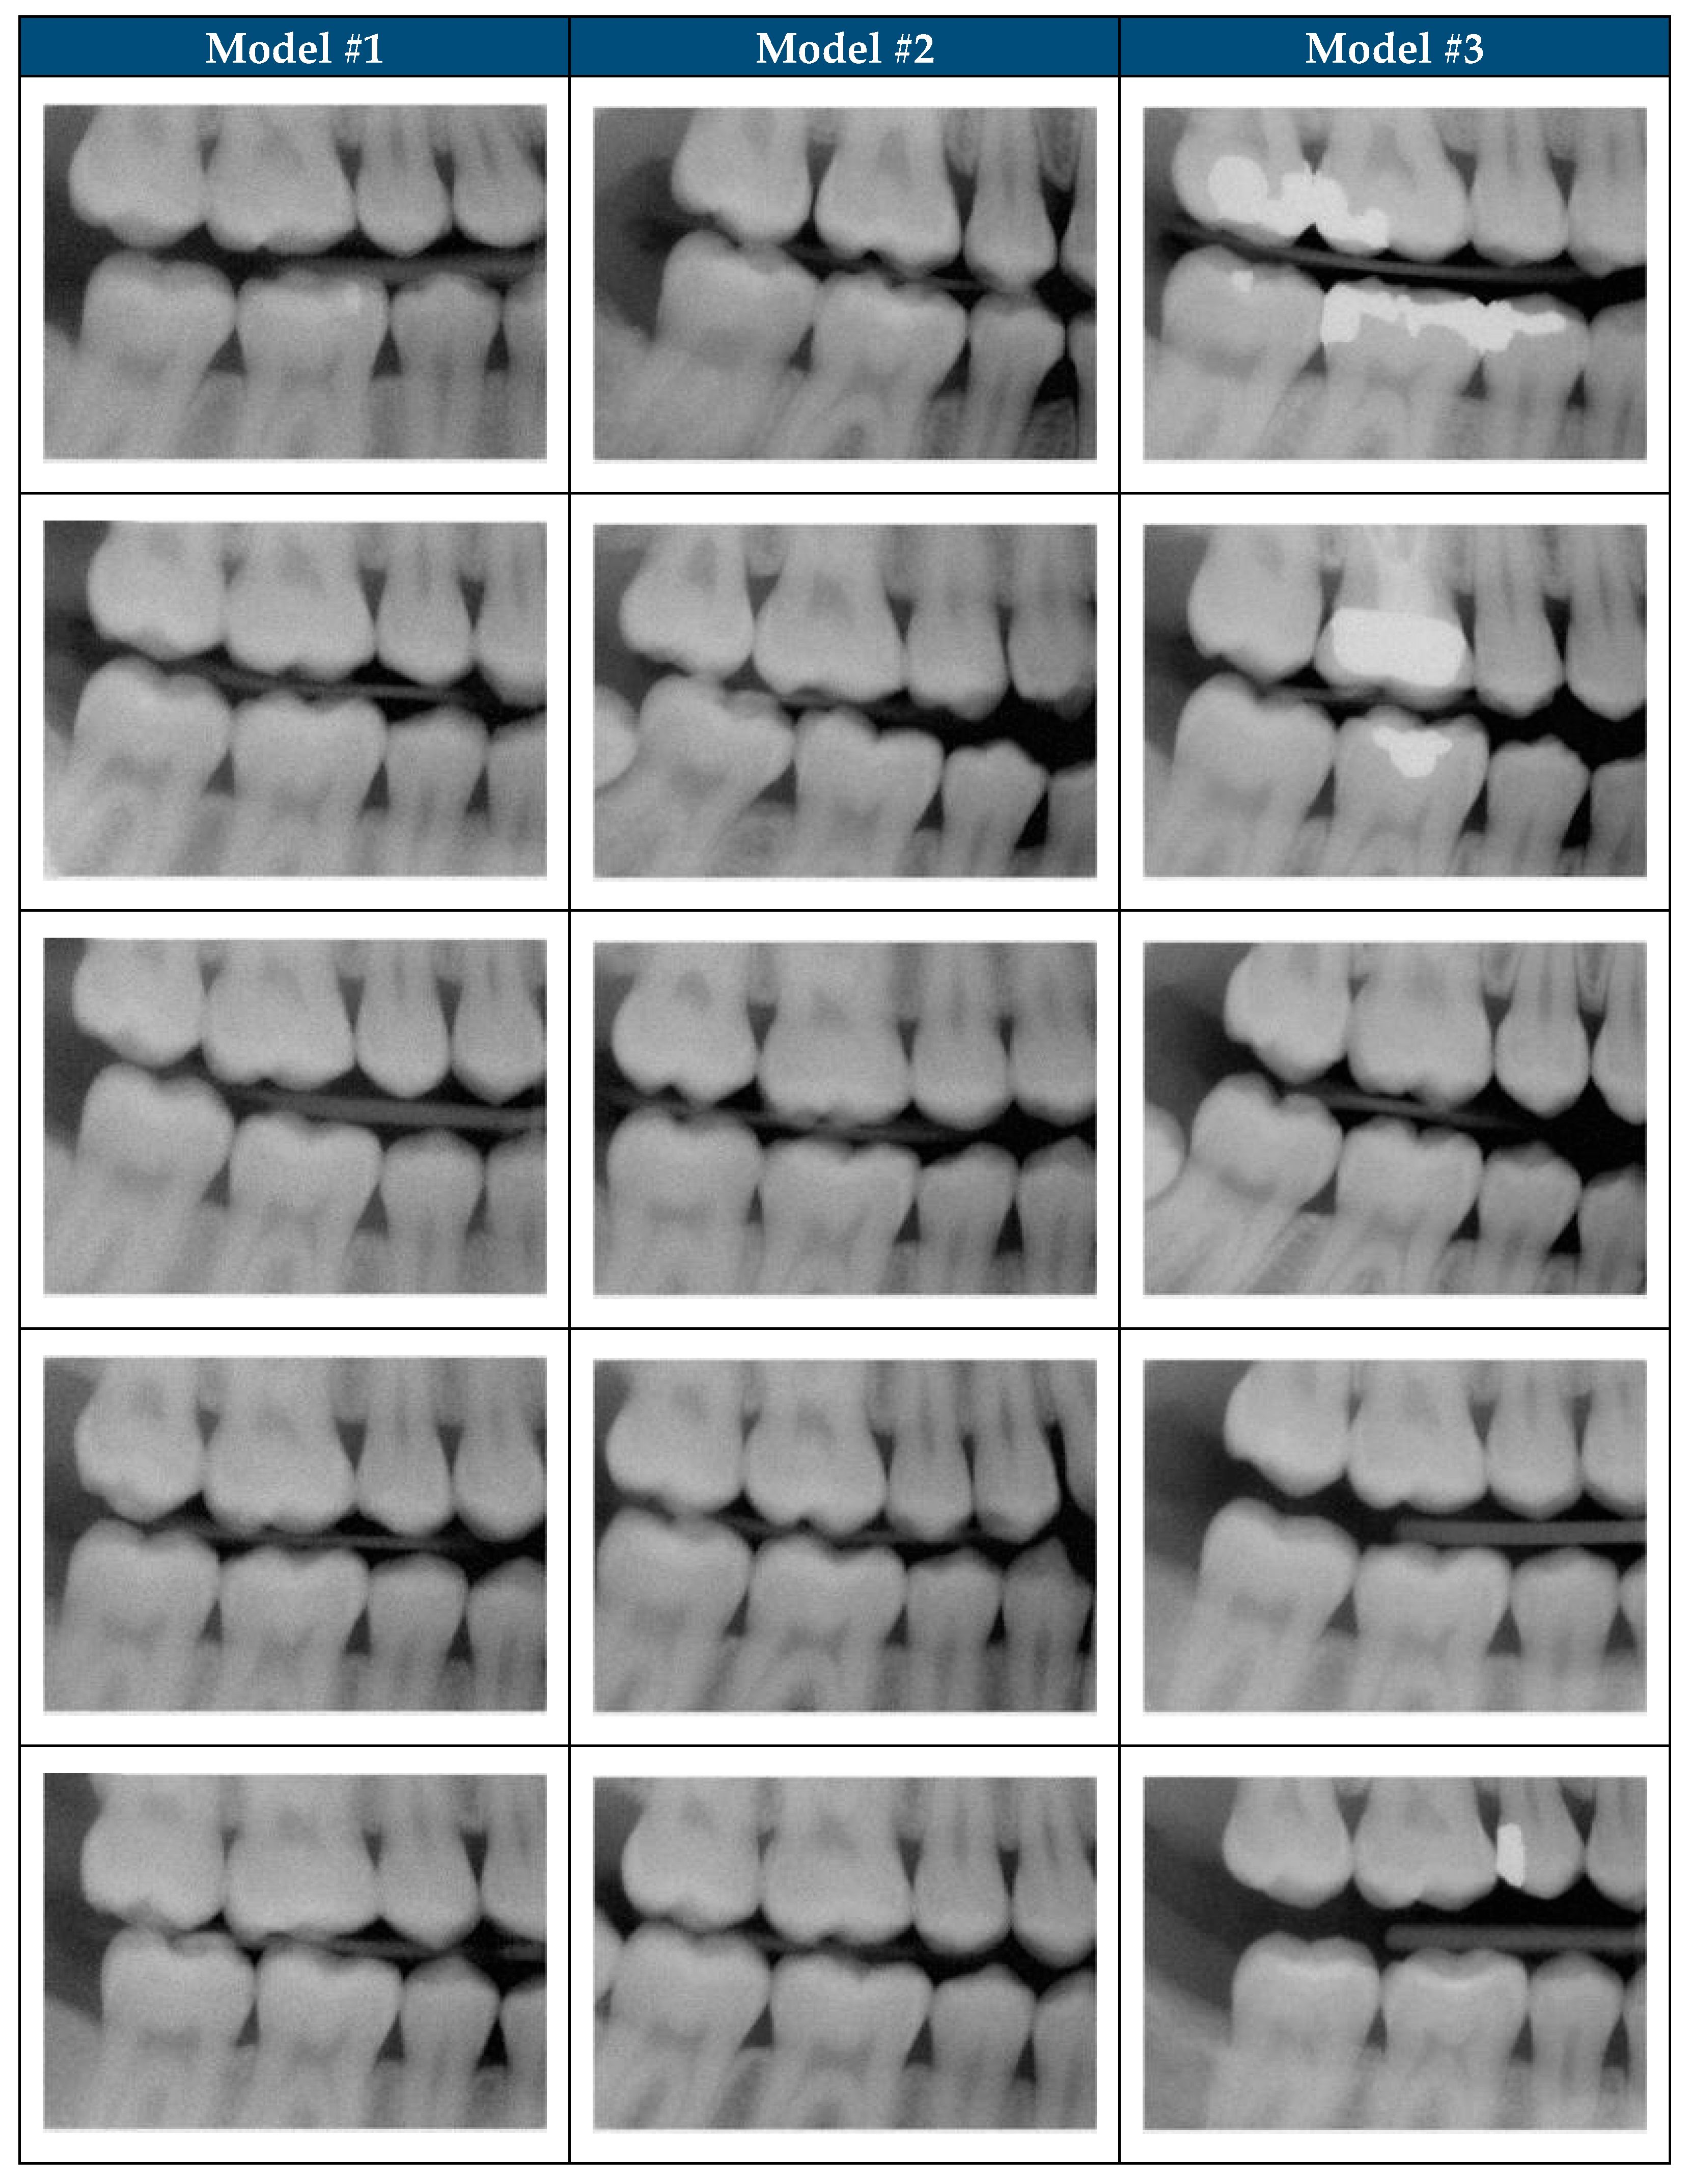

| Description | Model #1 | Model #1 | Model #1 | Model #2 | Model #3 |

|---|---|---|---|---|---|

| Training Dataset | |||||

| Total number of images | 200 | 200 | 200 | 200 | 200 |

| Number of unique images | 200 | 200 | 200 | 57 | 57 |

| Model Training | |||||

| Epochs | 22,000 | 30,000 | 40,000 | 30,000 | 30,000 |

| Diffusion steps | 300 | 300 | 300 | 300 | 600 |

| Model Performance | |||||

| Total SDR Graded | 500 | 500 | 500 | 500 | 500 |

| Number of Images Scored 1 | 28 | 74 | 9 | 110 | 451 |

| Number of Images Scored 2 | 120 | 51 | 34 | 109 | 42 |

| Number of Images Scored 3 | 88 | 146 | 35 | 134 | 3 |

| Number of Images Scored 4 | 263 | 214 | 379 | 139 | 4 |

| Number of Images Scored 5 | 1 | 15 | 43 | 8 | 0 |

| Average Score | 3.18 | 3.09 | 3.83 | 2.65 | 1.12 |

| Standard Deviation | 0.98 | 1.11 | 0.75 | 1.15 | <0.01 |

| Realistic SDR Generation rate | 6% | 15% | 2% | 22% | 90% |

| Model Refinements | |||||

| Refinement | Training Duration (Epochs) | Training Duration (Epochs) | Training Duration (Epochs) | Expert Panel Refined Dataset | Addition of 300 Diffusion Steps |

| Impact of Refinement on model performance (p-Value) | Worse (<0.05) | Improved (<0.05) | Worse (<0.05) | Improved (<0.05) | Improved (<0.05) |